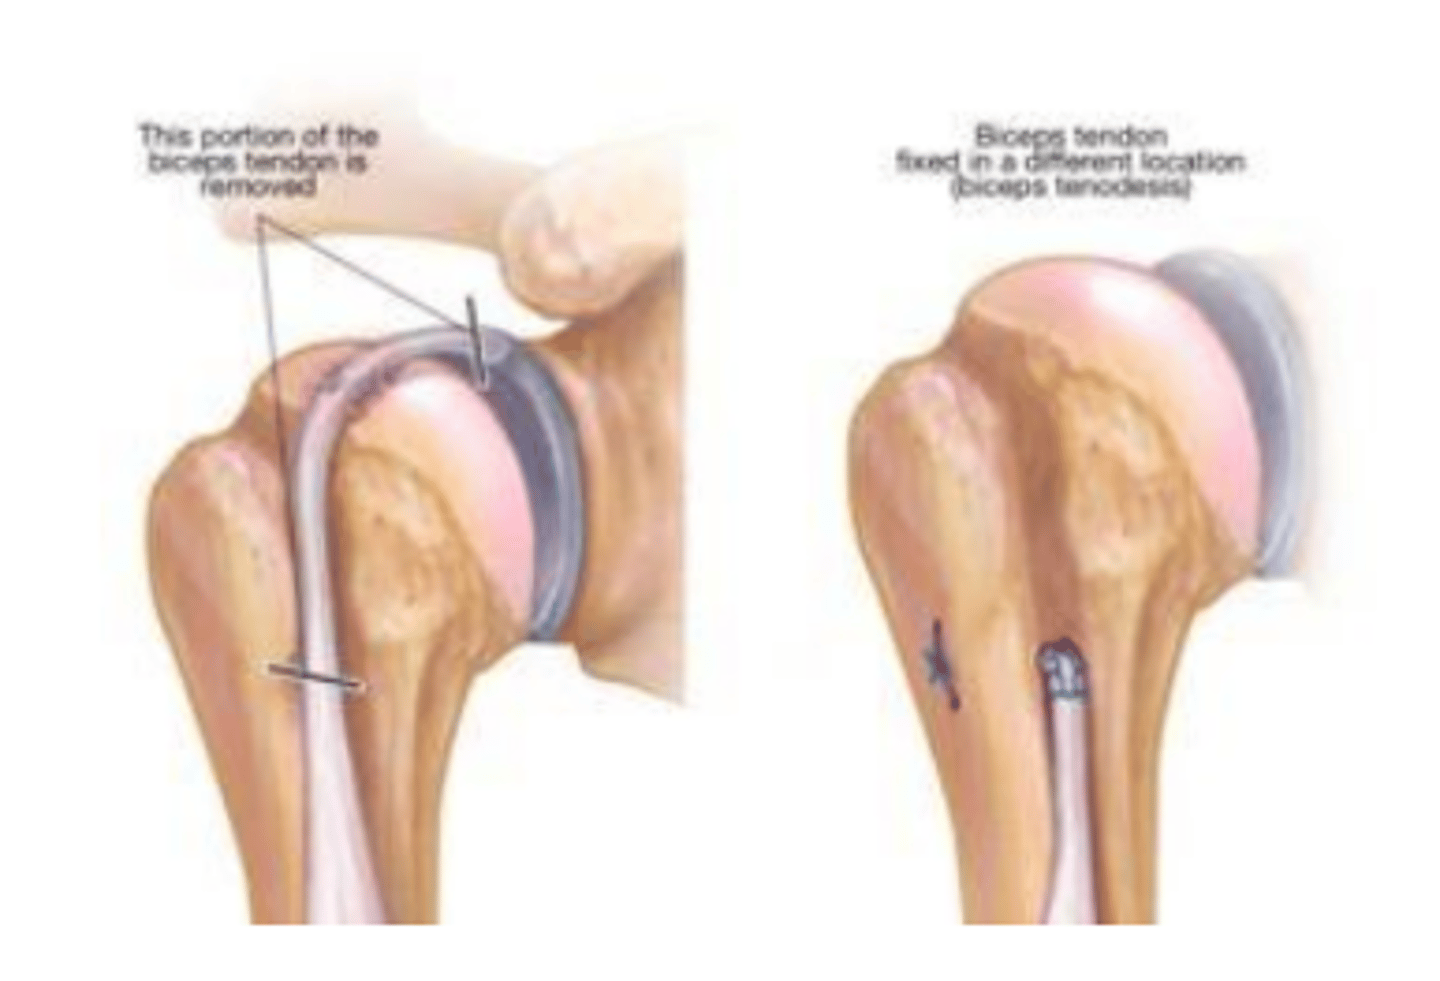

Bicipital tenodesis

Portion of the biceps tendon is removed and the tendon still intact is fixed is a different location.

Diseased

Bicipital tenodesis is performed when the bicep is involved in the SLAP tear or __________________ (causing pain).